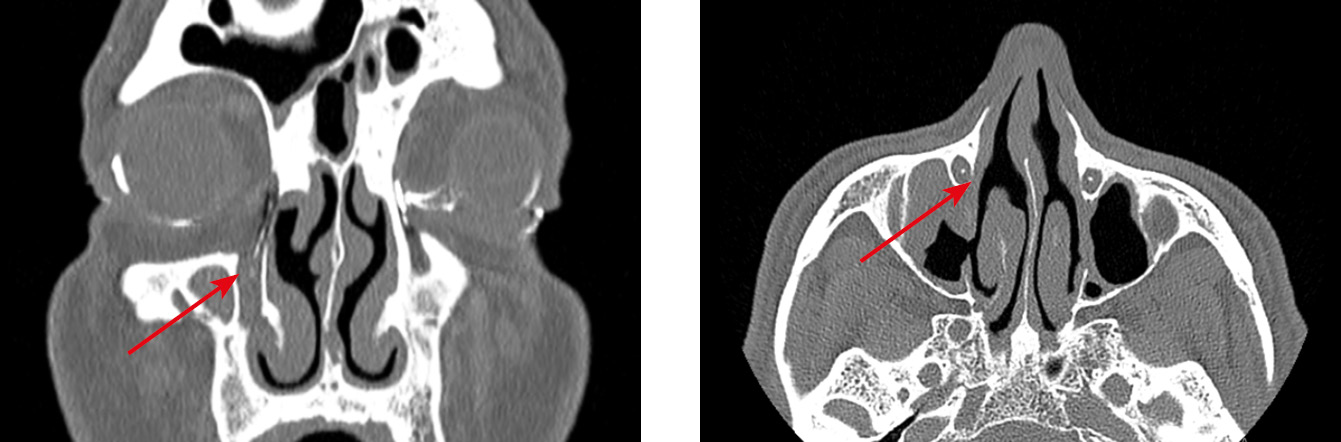

Интересен тот факт, что в двух случаях нашей серии нарушение проходимости СОП возникло после осуществления вмешательств на структурах наружного носа, а именно при проведении остеотомии в ходе ринопластики (рис. 8–10). По данным литературных источников, такие осложнения встречаются крайне редко, в основном при латеральной остеотомии [23, 24].

Рис. 8. Состояние после риносептопластики. Саккальная непроходимость слезоотводящих путей слева после проведения латеральной остеотомии (стрелки)

Fig. 8. Status post rhinoseptoplasty. Left lacrimal duct obstruction after lateral osteotomy (arrows)

Рис. 9. Двустороннее нарушение проходимости вертикального отдела слезоотводящих путей; слева — после проведения латеральной остеотомии на уровне верхней трети носослезного канала (постсаккальная непроходимость)

Fig. 9. Bilateral obstruction of the vertical part of the lacrimal ducts; on the left, status post lateral osteotomy at the level of the upper third of the nasolacrimal canal (post-saccal obstruction)

Рис. 10. Состояние после медиальной максиллотомии слева, септопластики. Хронический дакриоцистит (OS) с частичной проходимостью носослезного протока, дакриостеноз носослезного протока на уровне нижней трети носослезного канала (стрелка)

Fig. 10. Status post left maxillary medial sinusotomy, septoplasty. Chronic dacryocystitis (OS) with partial patency of the nasolacrimal duct, dacryostenosis of the nasolacrimal duct at the level of the lower third of the nasolacrimal canal (arrow)